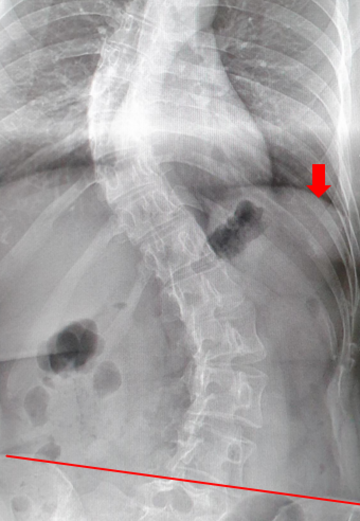

Vor der Operation

Schnell voranschreitende doppelbogige Skoliose bei einem 17 Jahre alten Mädchen. Beachten Sie die Beckenverkippung (rote Linie) und zusammenstehenden Rippen (roter Pfeil).

OP-Ergebnis

Harmonisch stehende korrigierte Wirbelsäule mit einer leichten Schultererhöhung, die sich unter Physiotherapie normalisiert hat (Rote Striche). Das Becken steht wieder gerade. Die Rippenstellung hat sich normalisiert.